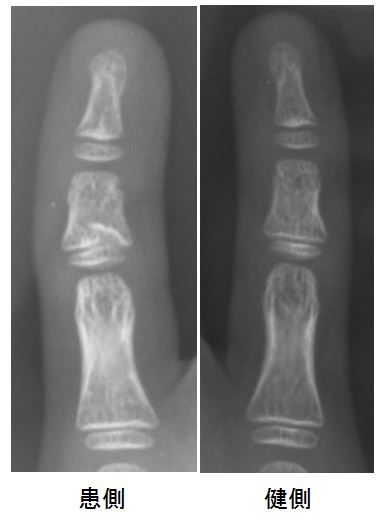

診察すると小指のPIP関節が腫脹しており、単純X線像は下記のごとくでした。

中節骨近位骨幹端が末梢方向に陥没しているようです。側面像でも掌側に小骨片を認めたことから、PIP関節捻挫ではなく中節骨近位骨端離開と判断しました。

しかし、未だかつてこのような画像所見を見たことがありません。詳細な受傷機転が不明のため何とも言えないのですが、消去法的に考えるとSalter-Harris type 5である可能性が高いです。

PIP関節面の不整が無いため、中節骨近位骨幹端は陥没(?)しているものの、このまま外固定で経過観察せざるを得ないと判断しました。